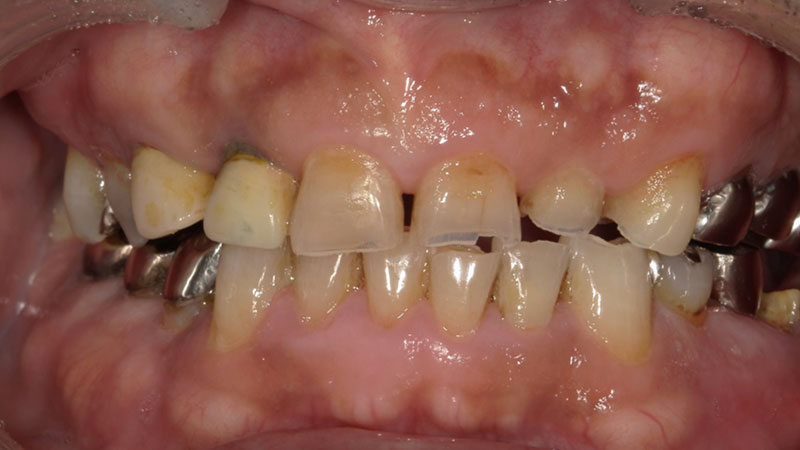

患者さんの悩みは抜歯した歯の部分を矯正で治したいのと、八重歯が気になること、上の歯の正中(真ん中)が合っていないことでした。

マウスピース矯正希望とのことだったので、アンカースクリューを用いてしっかりした固定を得て、空いたスペースに歯を動かすことをご提案いたしました。

患者さんの悩みであった前歯の見た目としっかりスペースを閉じ噛み合わせが改善されてとても喜ばれていました。

| 患者様 | 30代男性 |

| 主訴 | 上下前歯の重なりが気になる |

| 所見 | 右上第一小臼歯が欠損しているため、スペースを利用して犬歯・第一小臼歯、を遠心に移動する必要あり |

| 治療装置 | インビザライン、アンカースクリュー |

| 装置装着部位 | 全顎 |

| 治療費 | 矯正費88万円(税込) アンカースクリュー埋入費:33,000円(税込) |

| 治療期間 | 約2年4か月(約30回通院) |